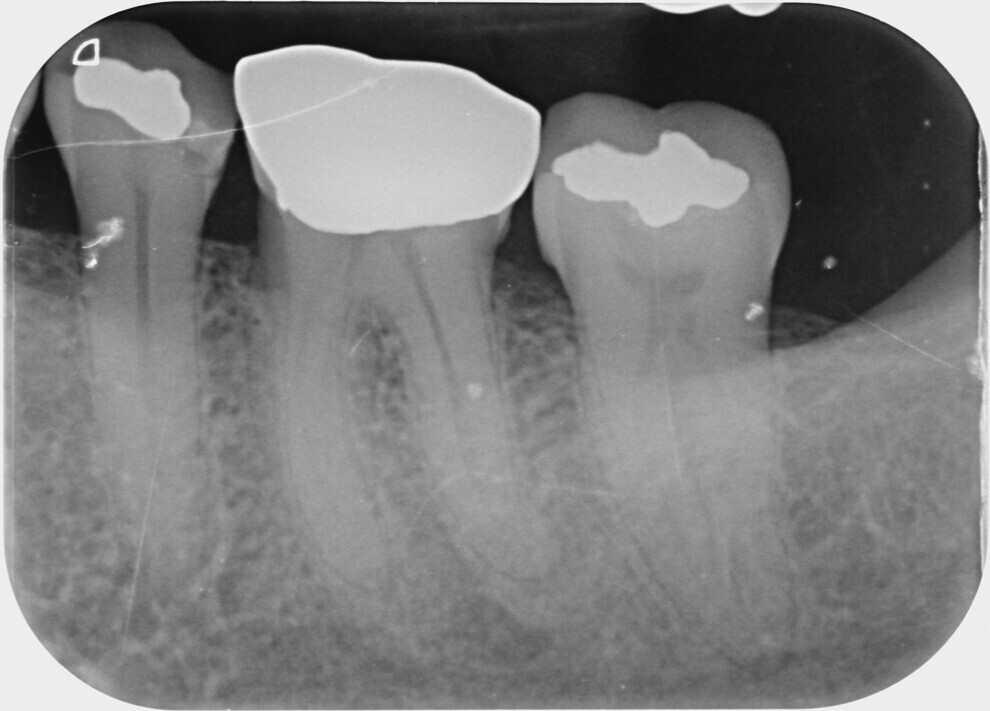

During a 30-second resting phase, the irrigant within the pulp chamber appeared to become cloudy. Number 10 files were placed in all the three canals until resistance was met, and all were restricted from passing 18 mm. A working length radiograph was taken (Fig. 2), and it showed that the files in the mesial canals had reached a point of constriction or obstruction which would not allow further access towards the apex. After a further five cycles of laser-assisted irrigation with 17% EDTA with a 30-second resting time and recapitulation with #10 and 15 files, the instruments were able to reach the apex at 22 mm in the distal canal and 21 mm in the mesiobuccal and mesiolingual canals (Fig. 3). This showed that the irrigant had successfully penetrated the canal system and dissolved the blockage that had prevented initial access to the apical segment. After the canals had been prepared with rotary files, the final irrigation protocol was done, initially allowing more cloudy liquid to float to the surface. At the completion of laser-assisted irrigation, the canals were dried with paper points, and no bleeding was observed.